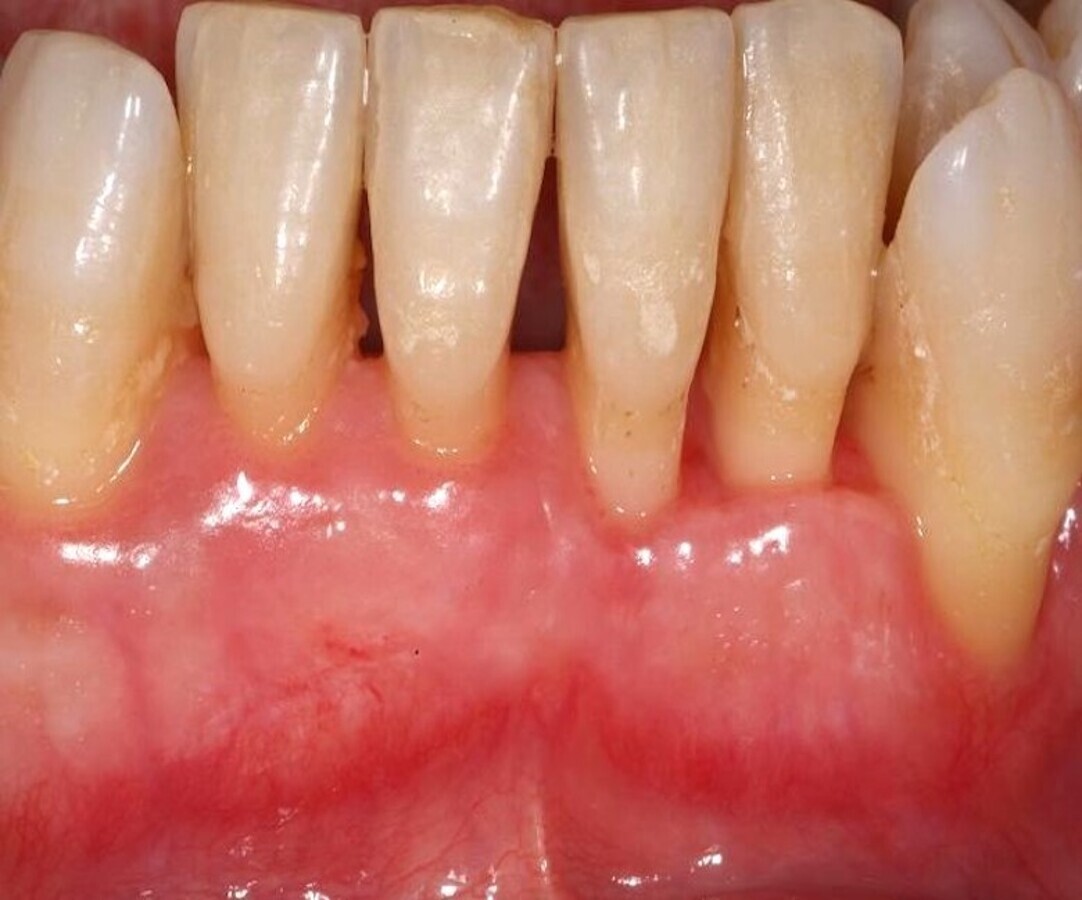

Este tratamiento se puede realizar mediante la técnica convencional (Figura 1), o con el láser de erbio, bien sea YAG o Er,Cr:YSGG (Waterlase) (Figura 2). Pero el uso del láser no elimina ni sustituye a las curetas, sino que las complementa, mejorando y potenciando el resultado del tratamiento (Figura 3).

Figura 1. El tratamiento de la enfermedad periodontal se puede realizar mediante la técnica convencional de raspado y alisado radicular.

El raspado y alisado radicular fue descrito hace muchos años por la Academia Americana de Periodoncia como un tratamiento meticuloso, arduo y que lleva tiempo, pero que al mismo tiempo y según la evidencia, ha demostrado ser muy eficaz en el control de la enfermedad periodontal. Si bien debemos considerar este tratamiento convencional como “gold standard”, no es menos cierto que puede ser complementado, simplificado e incluso mejorado con el láser.

La combinación del raspado y alisado radicular con el láser produce una mejoría clínica moderada en comparación con la técnica convencional, como constataron Borrajo y colaboradores1.

En otro estudio, Castro y colaboradores fueron más allá y concluyeron que además de lo anterior, el láser de diodo puede ser utilizado rutinariamente como complemento al raspado y alisado radicular sin que dañe el cemento radicular2. Esto debe darnos tranquilidad en cuanto al uso de esta tecnología en este tratamiento concreto y llevarnos a utilizarlo en nuestro día a día, siguiendo, eso sí, los parámetros de seguridad adecuados.